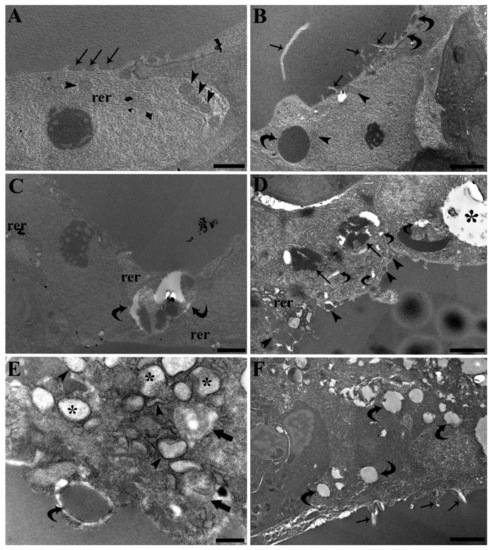

3.3. Follicle Ultrastructure

- Sakai, Y.; Yamashina, S.; Furudate, S.I. Missing secretory granules, dilated endoplasmic reticulum, and nuclear dislocation in the thyroid gland of rdw rats with hereditary dwarfism. Anat. Rec. 2000, 259, 60–66. [Google Scholar] [CrossRef]

- Schröder, M.; Kaufman, R.J. ER stress and the unfolded protein response. Mutat. Res. Fundam. Mol. Mech. Mutagen. 2005, 569, 29–63. [Google Scholar] [CrossRef]

- Manera, M.; Dezfuli, B.S.; Castaldelli, G.; De Pasquale, J.A.; Fano, E.A.; Martino, C.; Giari, L. Perfluorooctanoic Acid Exposure Assessment on Common Carp Liver through Image and Ultrastructural Investigation. Int. J. Environ. Res. Public Health 2019, 16, 4923. [Google Scholar] [CrossRef] [Green Version]

- Yan, S.; Zhang, H.; Wang, J.; Zheng, F.; Dai, J. Perfluorooctanoic acid exposure induces endoplasmic reticulum stress in the liver and its effects are ameliorated by 4-phenylbutyrate. Free Radic. Biol. Med. 2015, 87, 300–311. [Google Scholar] [CrossRef]

- Hocevar, S.E.; Kamendulis, L.M.; Hocevar, B.A. Perfluorooctanoic acid activates the unfolded protein response in pancreatic acinar cells. J. Biochem. Mol. Toxicol. 2020, 34, e22561. [Google Scholar] [CrossRef]

- Schmidt, F.; Wolf, R.; Baumann, L.; Braunbeck, T. Ultrastructural Alterations in Thyrocytes of Zebrafish (Danio rerio) after Exposure to Propylthiouracil and Perchlorate. Toxicol. Pathol. 2017, 45, 649–662. [Google Scholar] [CrossRef] [PubMed] [Green Version]

- Medelros-Neto, G.; Kim, P.S.; Yoo, S.E.; Vono, J.; Targovnik, H.M.; Camargo, R.; Hossain, S.A.; Arvan, P. Congenital hypothyroid goiter with deficient thyroglobulin: Identification of an endoplasmic reticulum storage disease with induction of molecular chaperones. J. Clin. Investig. 1996, 98, 2838–2844. [Google Scholar] [CrossRef] [PubMed]

- Néve, P.; Dumont, J.E. Time sequence of ultrastructural changes in the stimulated dog thyroid. Z. für Zellforsch. und Mikrosk. Anat. 1970, 103, 61–74. [Google Scholar] [CrossRef] [PubMed]

- Smith, C.J.; Gordon Grau, E. Ultrastructural changes in the parrotfish thyroid after in vitro stimulation with bovine thyrotropin. Fish Physiol. Biochem. 1986, 1, 153–162. [Google Scholar] [CrossRef]

- Nilsson, M.; Mölne, J.; Jörtsö, E.; Smeds, S.; Ericson, L.E. Plasma membrane shedding and colloid vacuoles in hyperactive human thyroid tissue. Virchows Arch. B Cell Pathol. Incl. Mol. Pathol. 1988, 56, 85–94. [Google Scholar] [CrossRef]

- Cheville, N. Ultrastructural Pathology: The Comparative Cellular Basis of Disease, 2nd ed.; Wiley-Blackwell: Ames, IA, USA, 2009; ISBN 9780813803302. [Google Scholar]

- Manera, M.; Castaldelli, G.; Fano, E.A.; Giari, L. Perfluorooctanoic acid-induced cellular and subcellular alterations in fish hepatocytes. Environ. Toxicol. Pharmacol. 2021, 81, 103548. [Google Scholar] [CrossRef]